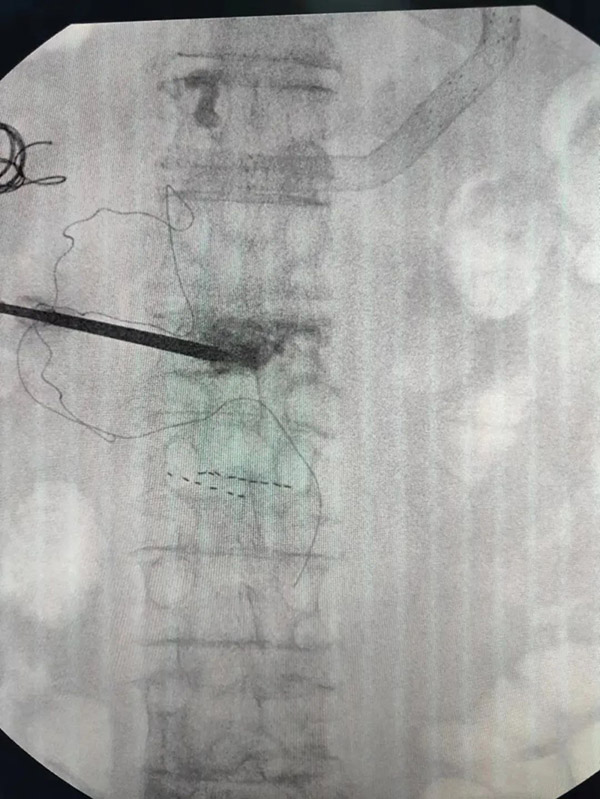

“没事儿,别怕,直起腰,正常走。现在走路是不是不疼了?”